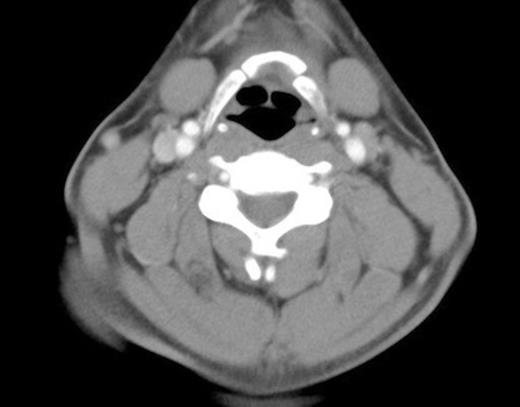

There was minor asymmetry of the valeculla and the left vocal cord (figure 2), but otherwise no significant airway compression. Management involved conservative treatment only with appropriate analgesia. On examination two weeks later, all his symptoms had settled. Repeat flexible nasal endoscopy showed only soft tissue swelling and minor asymmetry of the left valeculla.